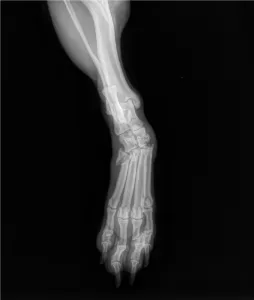

“La cosa più spontanea, l’ho portato a casa con me, a Colleferro, e ho pensato subito alle diverse pratiche. L’ho fatto visitare da un veterinario, mi ha detto che era in buone condizioni, non era denutrito e non aveva malattie, ma non riusciva a camminare. La zampa posteriore però era fratturata e quella anteriore aveva ricevuto una forte contusione. Ha subito iniziato una cura di due giorni, qualche anti-infiammatorio e antibiotico: ha ricominciato a muoversi”.

La zampa però va operata…

“Ho fatto un giro di chiamate partendo dalla Polizia, poi è stato prezioso il sostegno della guardia zoofila, e sopratutto dell’associazione locale ‘Mai più randagi’. Ora stiamo cercando di dargli una seconda vita. Abbiamo avviato una raccolta fondi con donazioni online per pagare l’operazione. Andrà ricostruita una parte di osso, gli dovranno mettere delle placche. Il target minimo del preventivo di circa 700 euro è stato già raggiunto, ma sicuramente ci sarà bisogno di altre cure, controlli, di coprire i costi per le visite e per il periodo post-operatorio, chi vuole può darci una mano, manca ancora un po’ di tempo all’intervento che è stato programmato il 13 ottobre”.